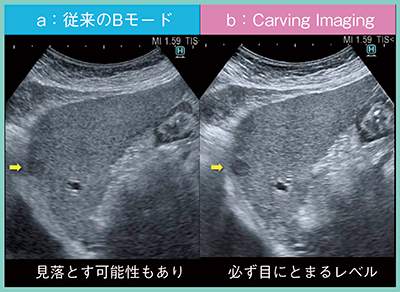

症例1は,78歳,女性,非アルコール性脂肪性肝炎(NASH)から肝硬変を来し,これまでに計3つの肝細胞がんに対してラジオ波焼灼療法(RFA)を繰り返している。さらに,2018年11月に認めた小さな低エコー結節が,2019年3月には9mmにまで増大していた。この低エコー結節は,従来のBモードでは見落とす可能性もあるが(図2 a),Carving Imagingでは必ず目にとまるレベルで描出されている(図2 b)。肋弓下からのあおり走査でも,Carving Imagingでは病変をはっきりと指摘でき,さらに,高周波プローブを使用することで,病変がきわめて明瞭となった(図3)。このように,Carving Imagingを用いることで,小病変でも病変構造の視認性が向上することがわかる。

図2 症例1:従来のBモードとCarving Imagingの画像比較

(肝細胞がん)